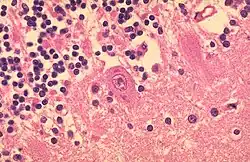

Typische große intranukleäre Einschlußkörperchen mit klarem Halo bei CMV-Infektion der Niere.

LANGHANS-Riesenzellen in einem Tbc-Granulom, transbronchiale Biopsie

Fremdkörper-Riesenzellen bei Aspirationspneumonie, Autopsiepräparat, H&E.

Riesenzelle und diffuser Alveolarschaden bei SARS-Infektion.

Riesenzelle mit intrazytoplasmischen inclusion bodies bei Masernpneumonie, Histopathologie.